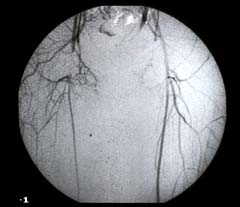

Intra-arterial Angiogram

An angiogram (digital subtraction angiogram or DSA) produces a road map of the blood vessels. It is a good way of examining the anatomy of the blood vessels and tells the surgeon which blood vessels are open and which are diseased, narrowed (stenosed) or blocked. More information is available by clicking here. Angiography is the most commonly used method of assessing the arteries before surgery.

It has one major disadvantage compared with the other techniques because it requires the placement of a needle inside the artery. This can be uncomfortable, but it is the only method of assessment, which can also be used to treat arterial disease by angioplasty. In addition angiography is the gold standard investigation in determining whether arterial narrowing or occlusion is present.